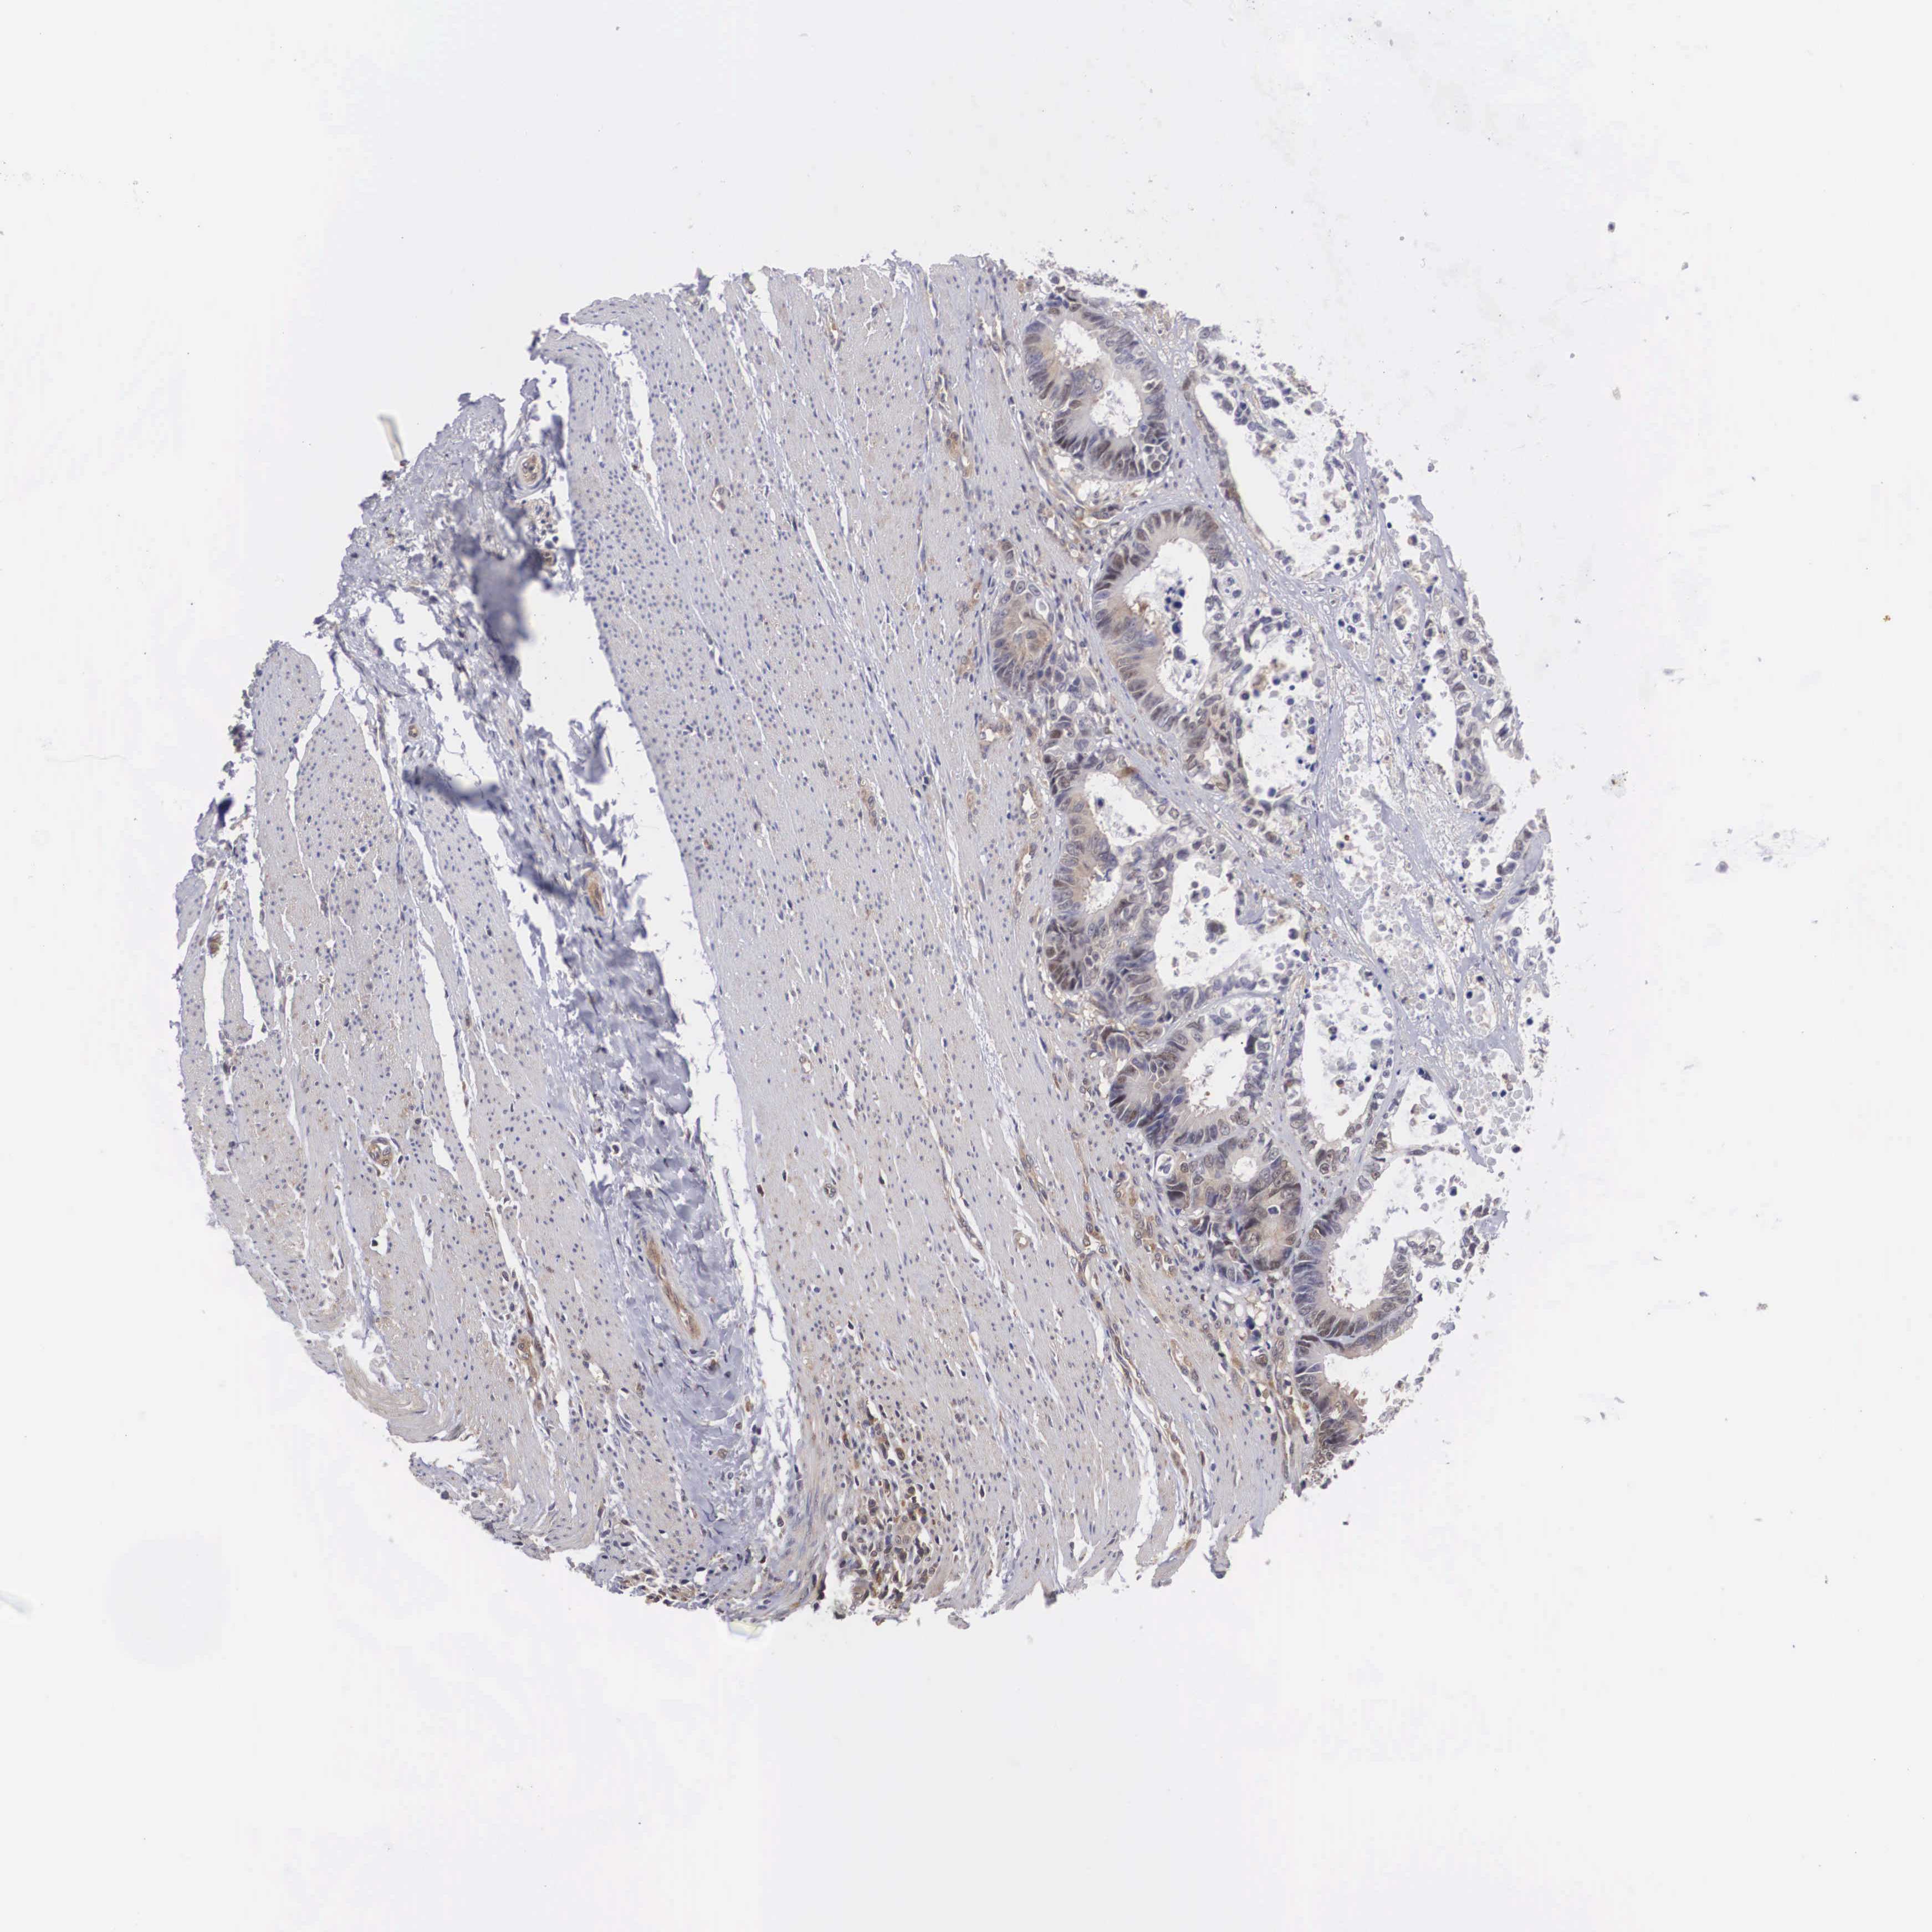

CANCER COLORECTAL CANCER Show tissue menu

ANTIBODIES

AND

VALIDATION